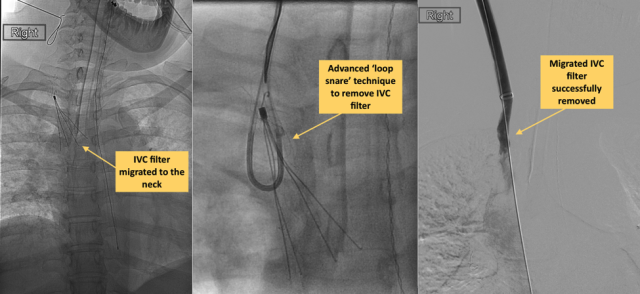

On rare occasion, an IVC filter can migrate after being placed and move to the heart, lungs or another blood vessel and cause damage there. The expert team of Interventional Radiology physicians at UCLA are equipped in removing all filters, including ones that have migrated.